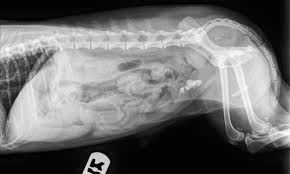

Overview stones of the urinary tract begin as microscopic crystals that aggregate to form stones of variable size and shape anywhere within the urinary system including the kidneys ureters and urethra although stones of the urinary bladder are most common. Cystine stones excessive elimination of cystine in the urine is an inherited disorder of kidney tubular transport that is thought to be the primary cause of cystine stones figure 5. Follow up appointments for urinalysis and or abdominal x rays should be done every 4 6 weeks after treatment initiation to ensure stones are dissolving and new ones are not forming.

These techniques are helpful to provide the outline of the stones in your dog s kidney. Kidney stones in dogs happen when crystals or stones form in the kidneys usually due to an abnormal concentration of mineral salts in the urine. Dogs with small kidney stones really may show no signs at all.

Herbal treatment at dr. A pica case confused with renal and bladder stones source. These images can be fetched after conducting tests using abdominal x ray contrast radiography or ultrasound equipment.

Canine kidney stones diagnosis. Kidney stones may show up on x rays of the belly that are being taken for unrelated reasons as a so called incidental finding for instance they may be discovered when you think your pooch may have eaten something he shouldn t have like one of your favorite earrings. There are several types of bladder stones.